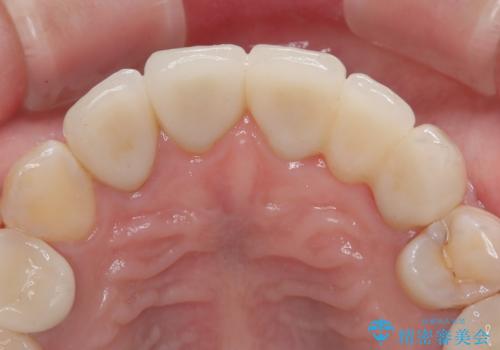

結婚式が近いことから、前歯は舌側に転位している歯は抜歯してブリッジにすることで外見と清掃性を改善し、速やかにオールセラミッククラウンにて補綴治療を行うこととしました。

前歯をブリッジとするか否か、非常に悩まれていらっしゃいましたが、術前と比べてものが挟まる感覚がなくなったとのことで、大変満足されていました。